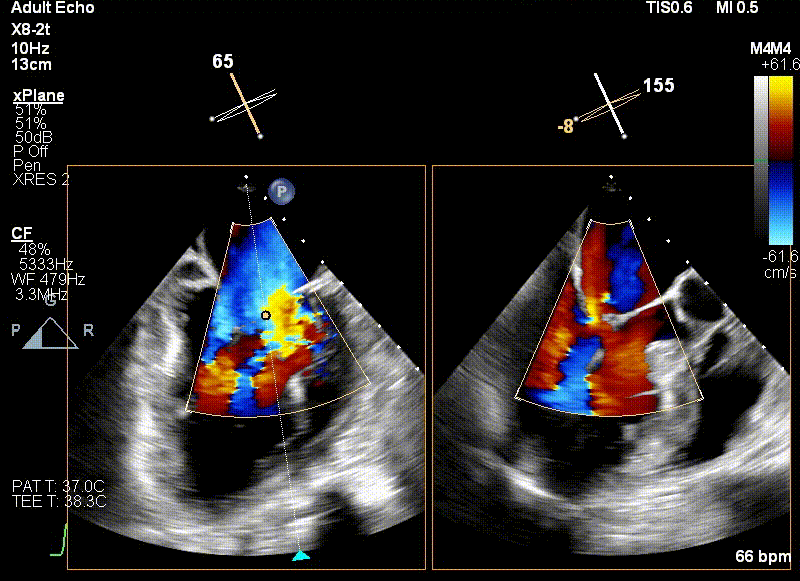

经食道超声引导后,王建安教授将二尖瓣夹NTR夹取C1区瓣叶,准确成功捕获C1前叶和后叶反流最严重区域,并予夹合。使二尖瓣在收缩期由大的单孔变成一大一小的双孔,显著减少了二尖瓣反流。

王建安教授与直播在线专家充分沟通讨论手术方案,为了进一步优化手术结果,计划打开二尖瓣夹后倒置夹臂再回拉至左心房,再次优化二尖瓣夹方向及位置后,多次反复尝试捕捞并夹持瓣叶。

反复测试二尖瓣夹的稳定性,食道超声复查提示二尖瓣夹C1区反流有效改善,术后反流量由术前的4+变为术后的<1,遂精准释放二尖瓣夹。